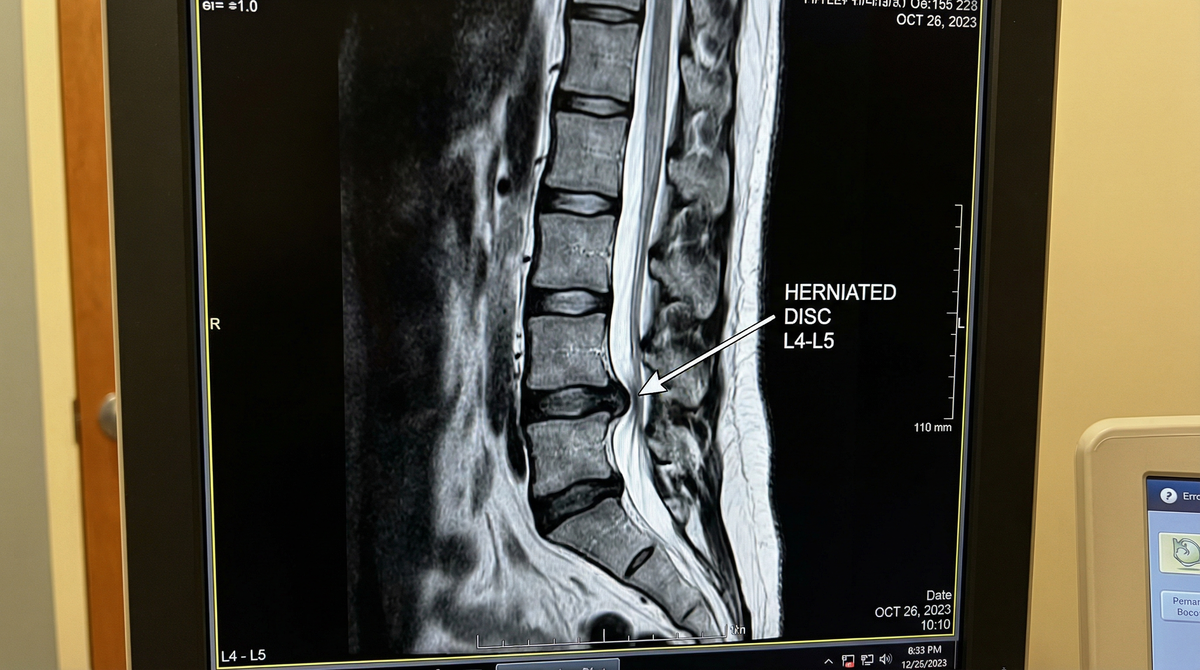

Свежий случай из практики

• Разберем ваши МРТ-снимки.